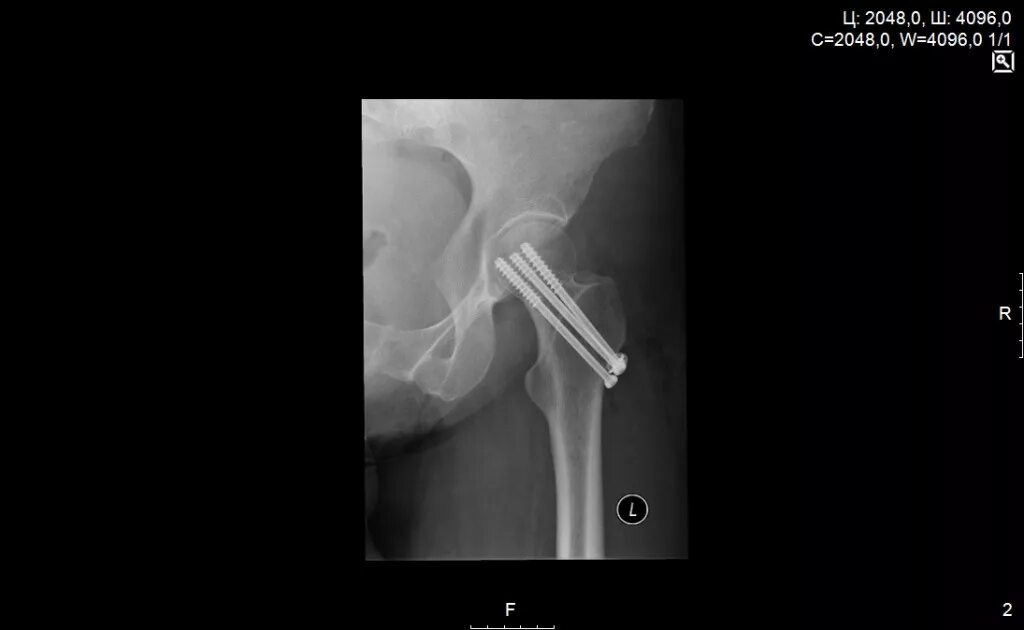

Перелом шейки бедра симптомы как определить